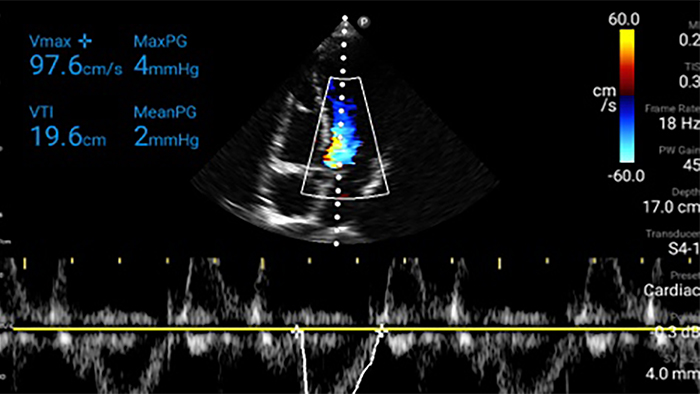

Un paciente con disnea

Ultrasonido cardíaco en el punto de atención prehospitalario: embolia pulmonar